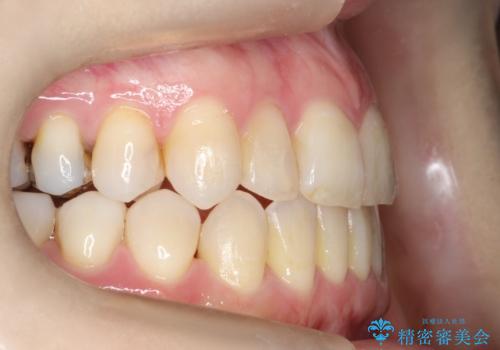

- 左上の八重歯の改善を希望され来院された患者様です。

初診時の歯並びの状態としては、上下ともに前歯部中心としたの中等度のがたつき(叢生)があり、全特に左上の前歯は1本だけ引っ込んでおり、犬歯は外に飛び出した状態でした。

抜歯は行わず上顎の奥のスペースを利用して歯をスライドする方法の他に歯列弓の拡大やディスキング(歯と歯の間の隙間を作る処置)を行い叢生を改善しましています。

歯の大きさの不揃いが原因の正中のズレは、ディスキング量を調整することで合わせました。

矯正装置としてはマウスピースを使用しています。

見た目、嚙み合わせ及び、治療期間や施術内容に大変ご満足いただきました。